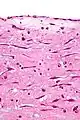

Atrial myxoma. H&E stain.

Atrial myxoma. H&E stain. -